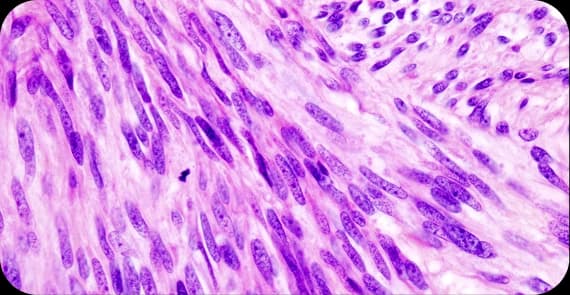

There are different types of ovarian cancer depending on the cell origin.

The most common type of ovarian cancer arises from the surface cells of the ovary.

Develop from egg-producing cells and are more common in younger women.

Arise from hormone-producing cells within the ovary.